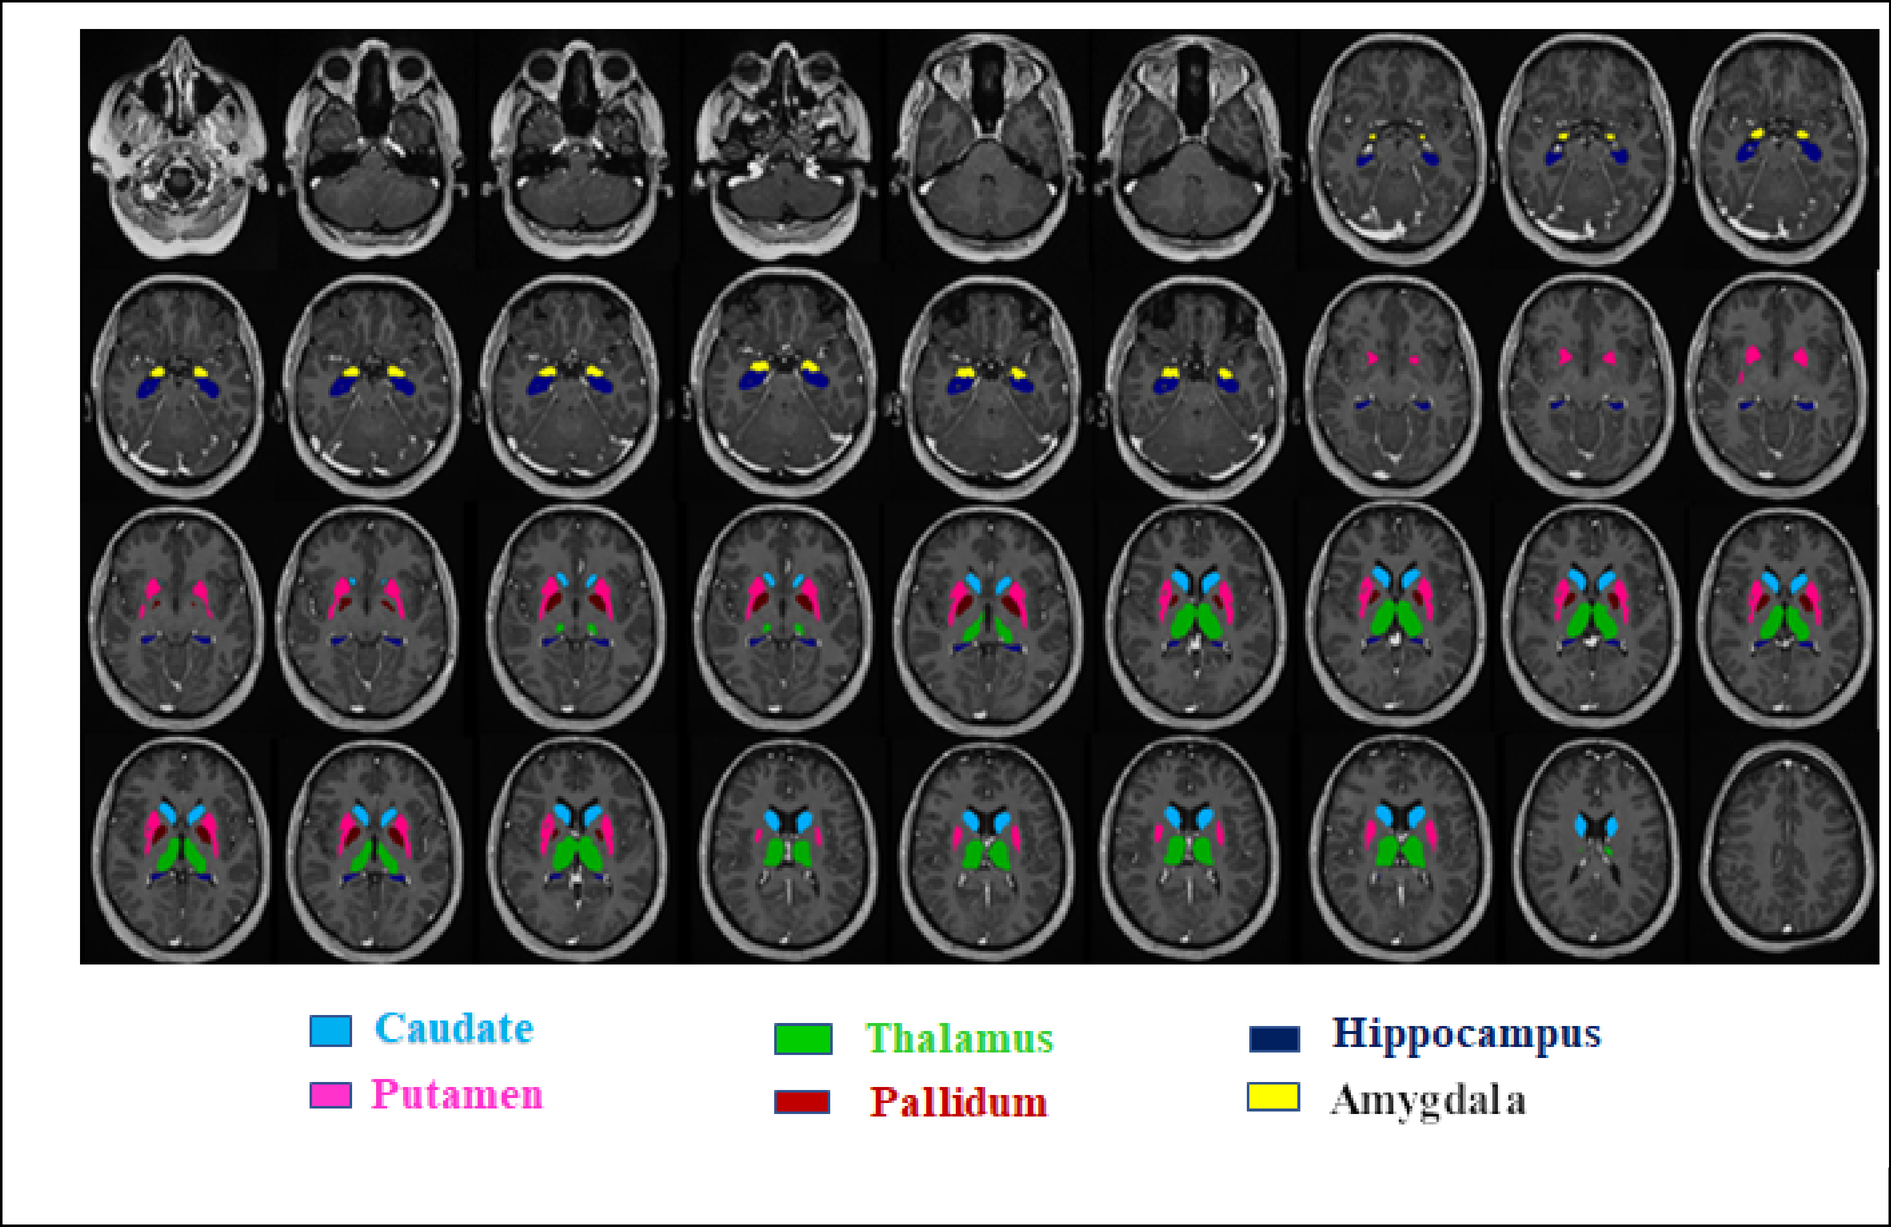

Fig. 2

Representative axial T1-weighted MR images illustrating automated segmentation of subcortical structures using the VolBrain: caudate, putamen, thalamus, pallidum, hippocampus, and amygdala.